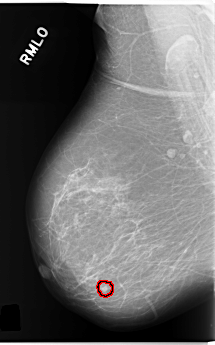

C_0253_1.RIGHT_MLO

RIGHT_MLO LINES 5856 PIXELS_PER_LINE 3640 BITS_PER_PIXEL 12 RESOLUTION 50 OVERLAY

FILE: C_0253_1.RIGHT_MLO.OVERLAY

TOTAL_ABNORMALITIES 1

ABNORMALITY 1

LESION_TYPE CALCIFICATION TYPE PUNCTATE DISTRIBUTION CLUSTERED

LESION_TYPE MASS SHAPE OVAL MARGINS CIRCUMSCRIBED

ASSESSMENT 4

SUBTLETY 5

PATHOLOGY BENIGN

TOTAL_OUTLINES 1

BOUNDARY